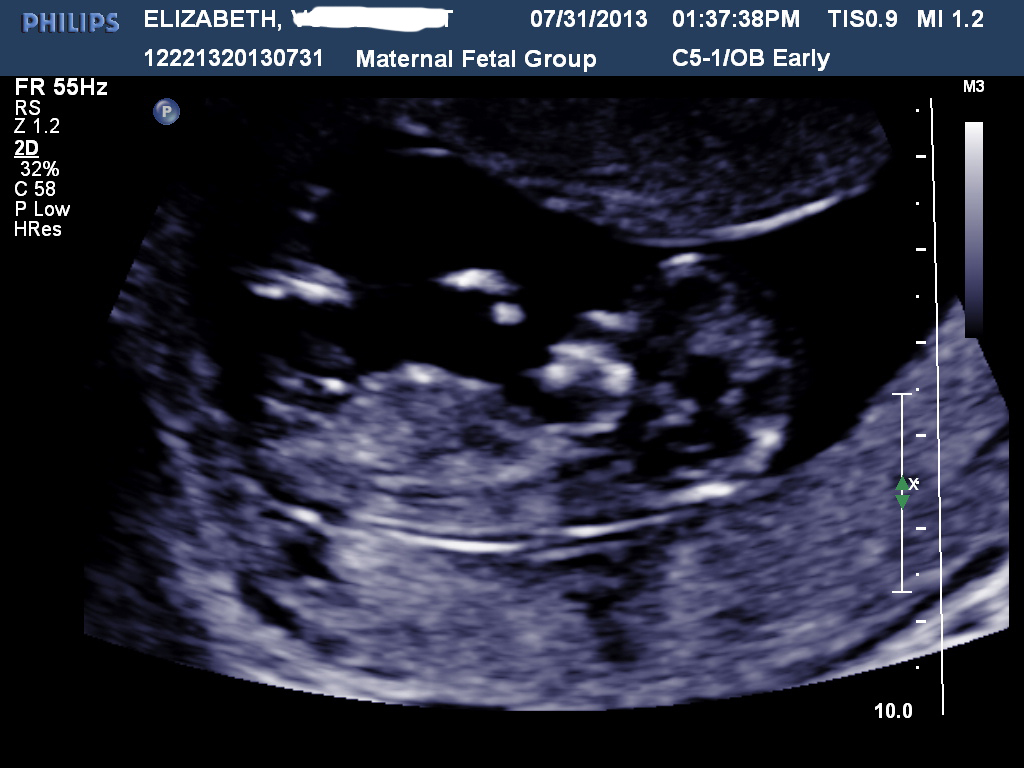

Hi all! I had my NT scan today and I'm stumped. There was no denying that my son was a boy but this baby has left me pretty stumped. I've gotten some mixed reviews elsewhere but it tends to lean one way over the other... Taken at 12w4d. So, predictions? :)

Attachment 12739